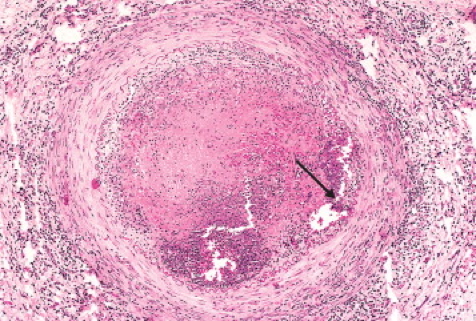

- Biopsy: granulomatous inflammation

Granulomatous inflammation around small vessels with epithelioid cells and giant cells.